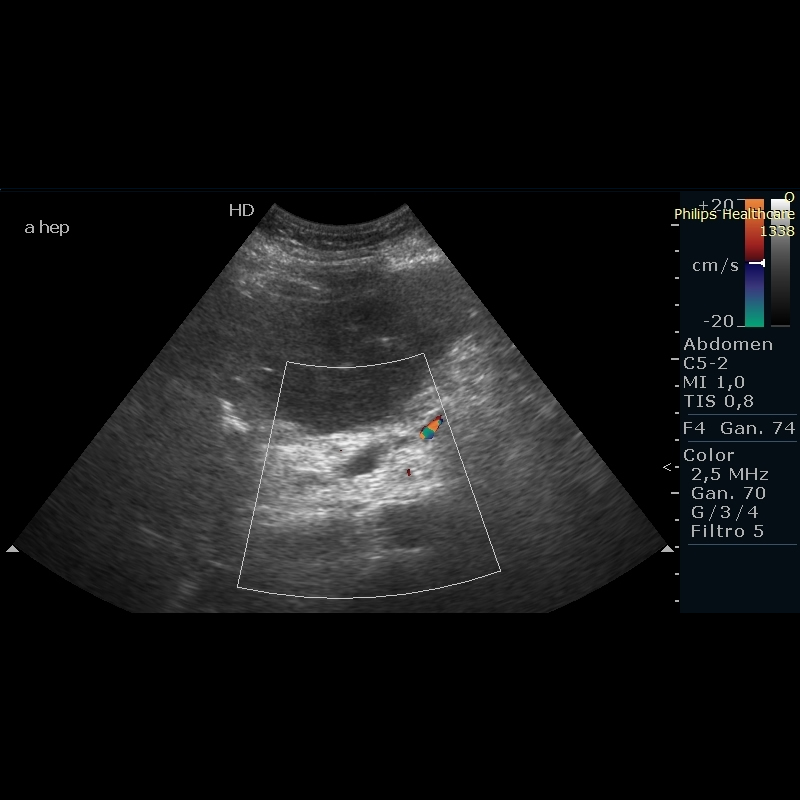

Motivo de consulta: Dolor abdominal